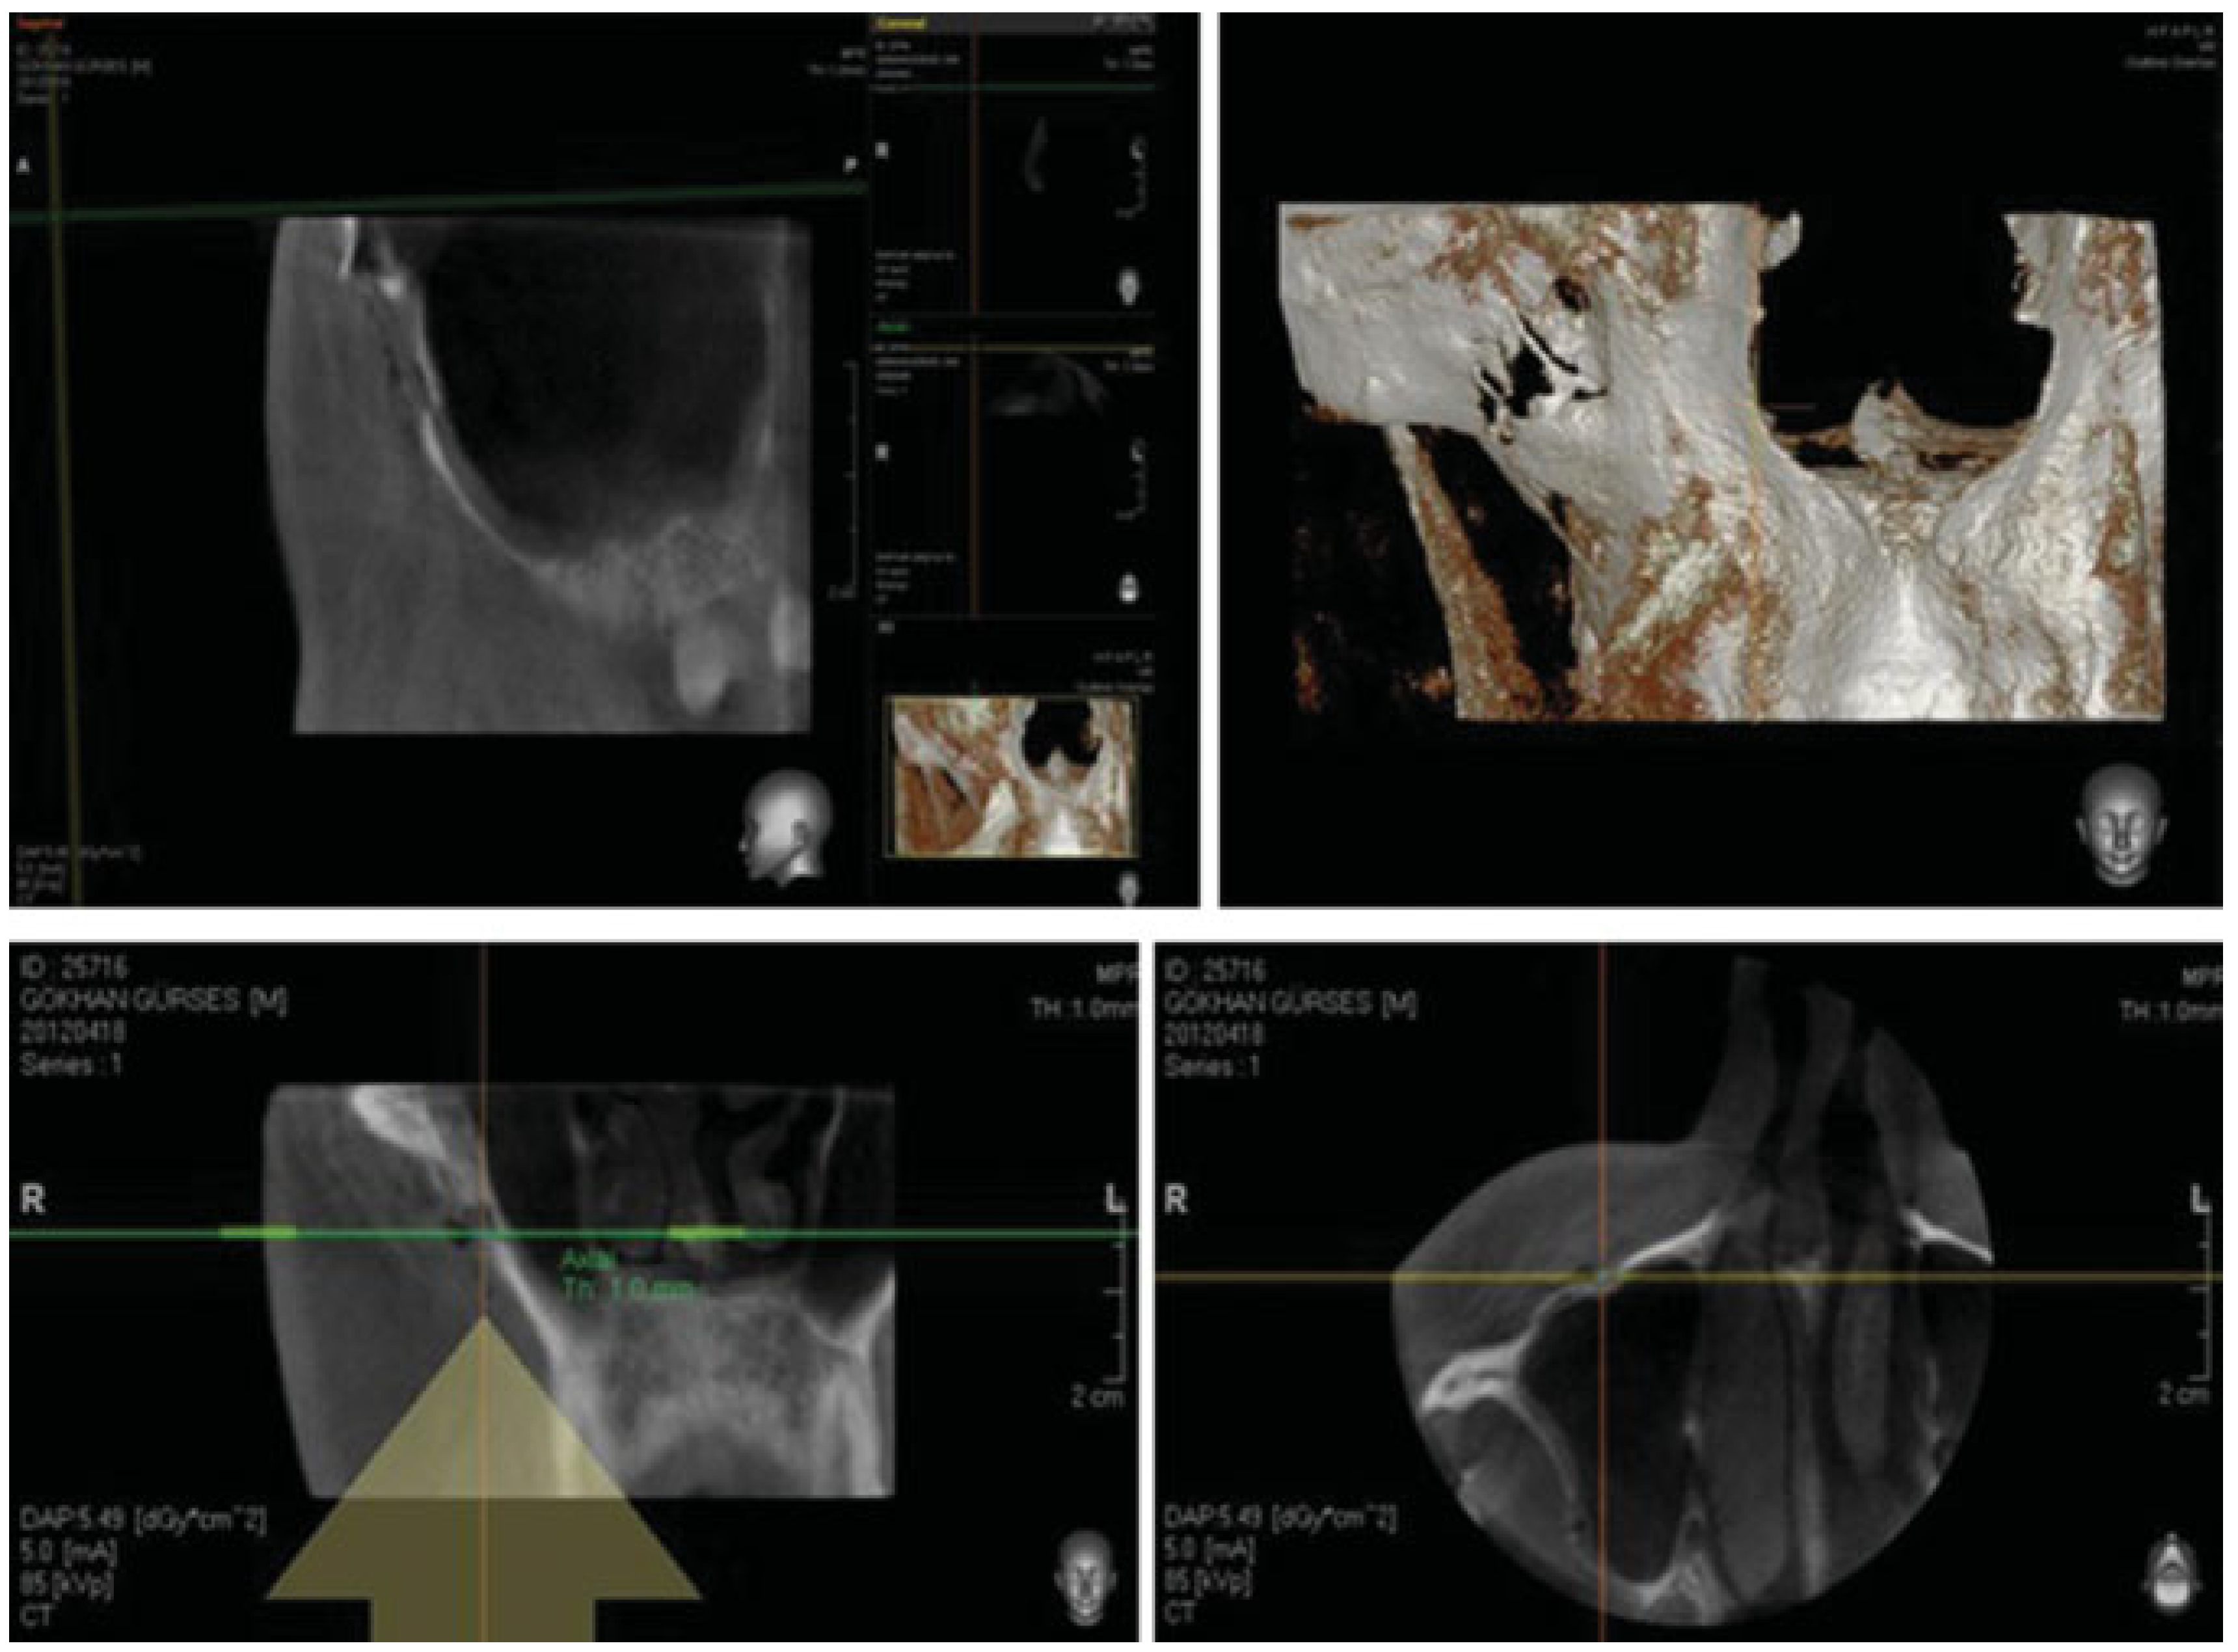

Case Report